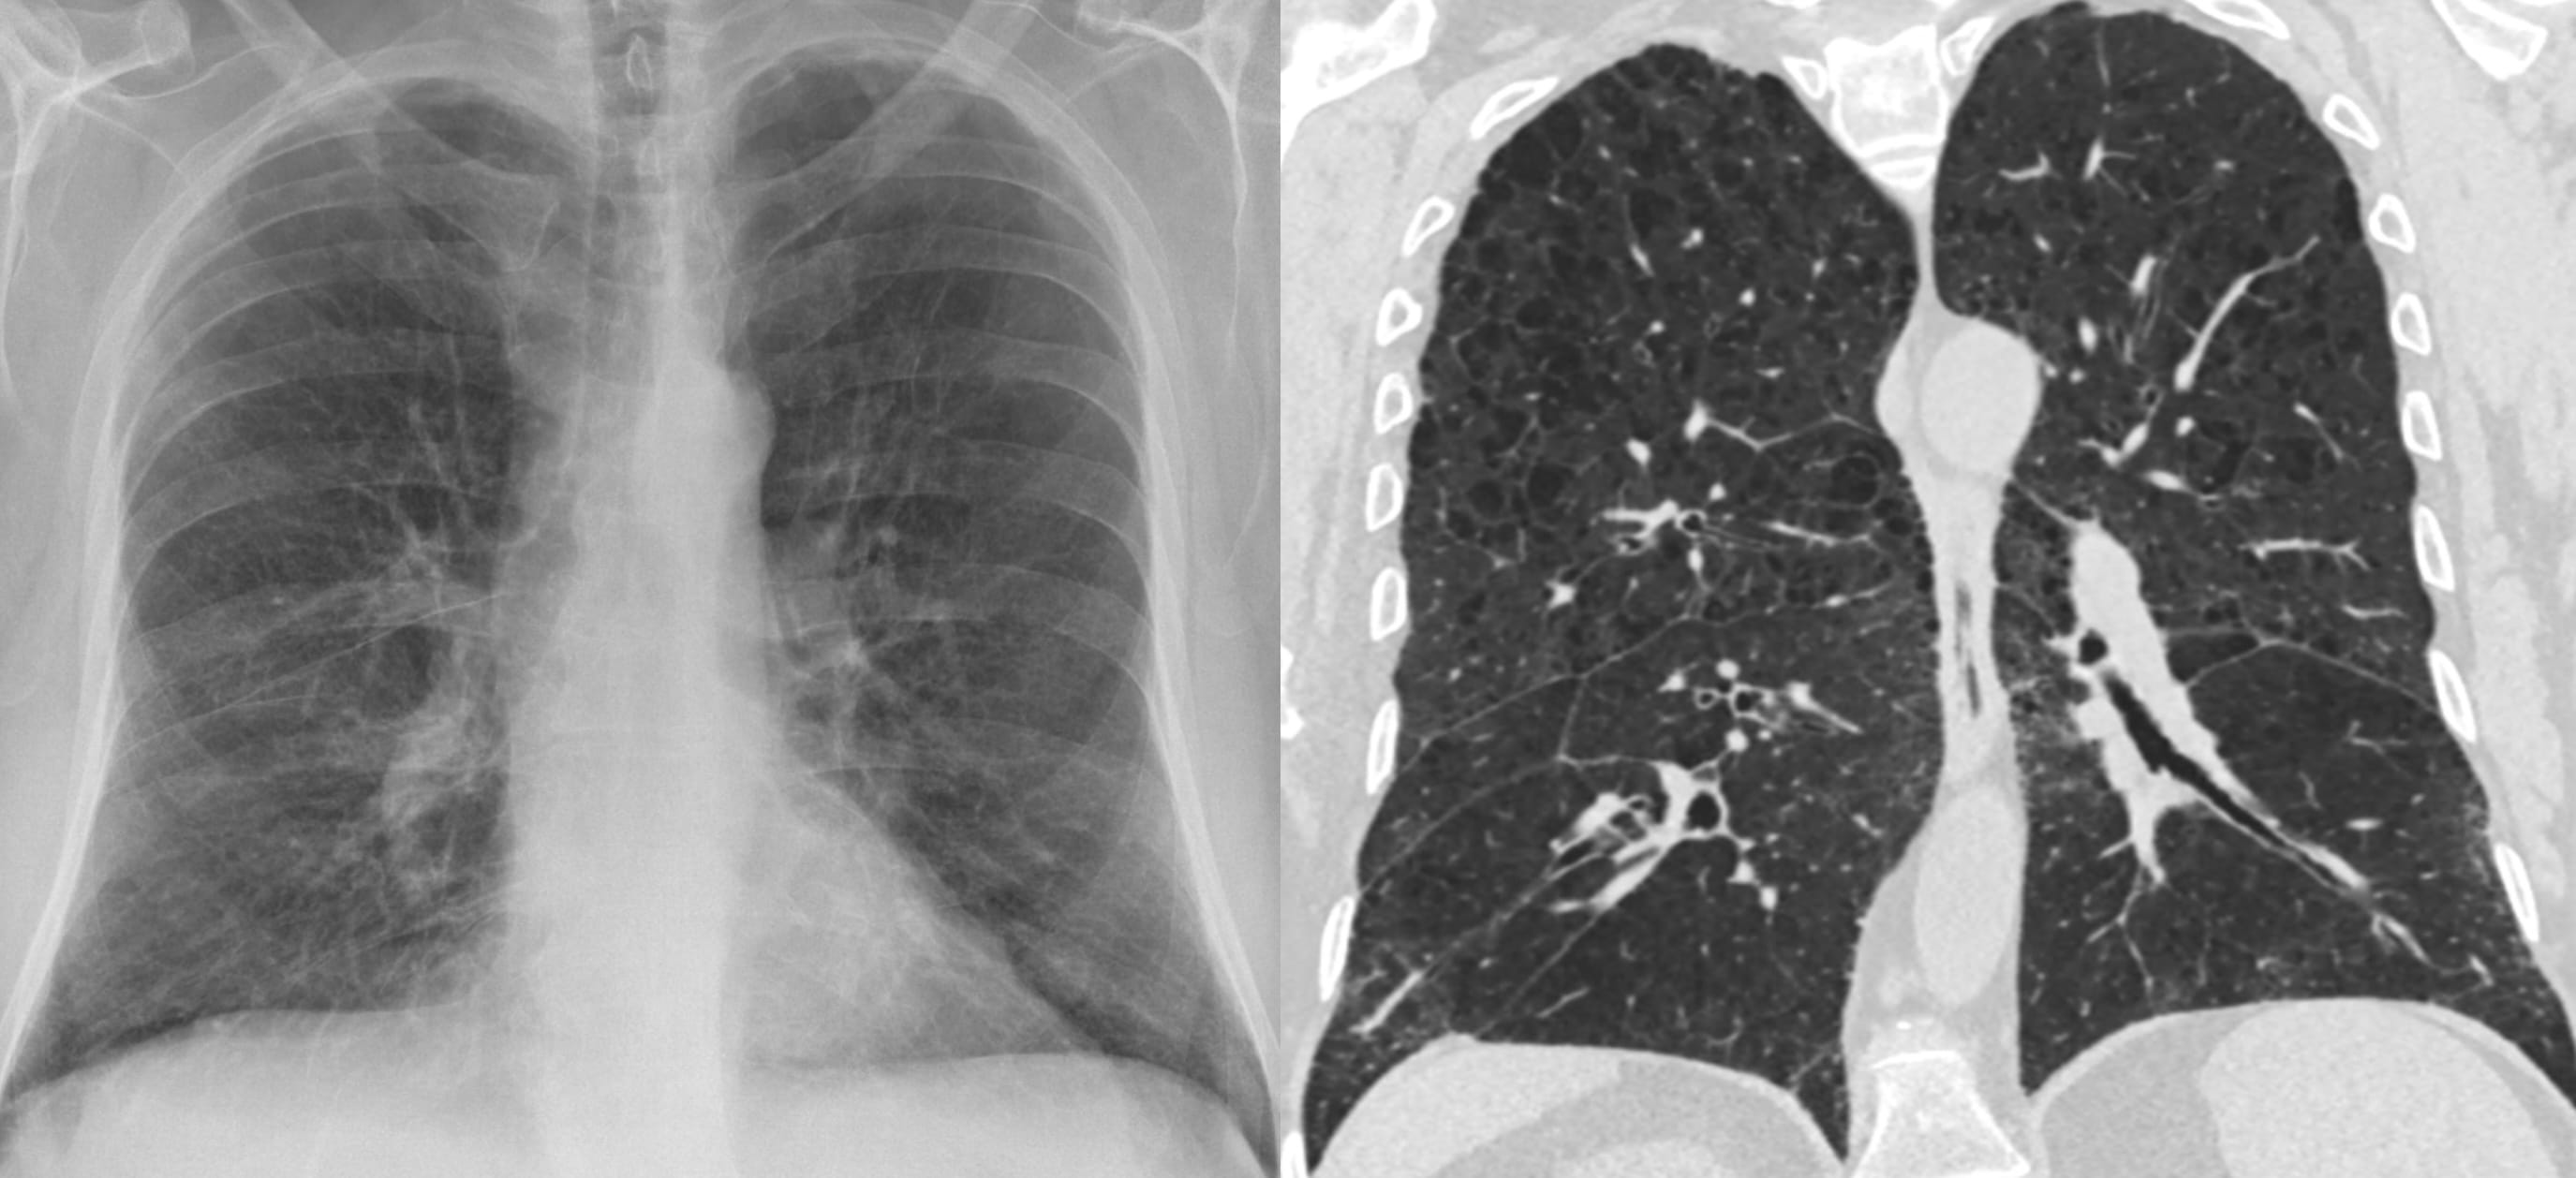

- Fibrotic Hypersensitivity Pneumonitis